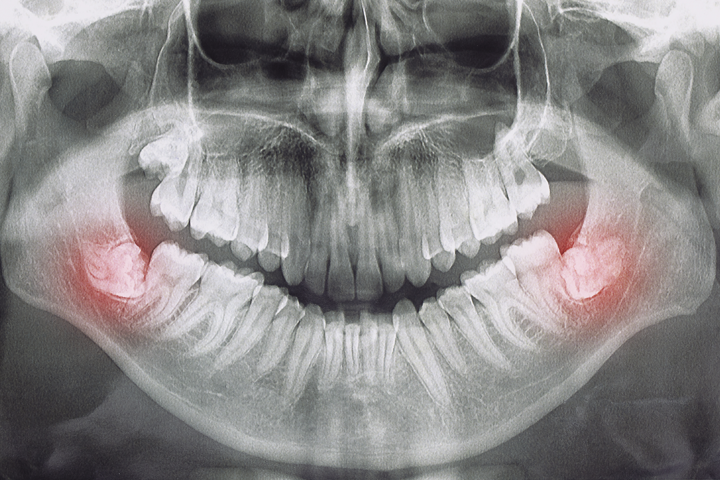

Extracción de muelas del juicio

Las muelas del juicio, son el tercer molar. Se encuentran situados en la última posición de la línea de la dentadura, tanto en la parte superior como inferior de la boca. Estas cuatro muelas suelen salir entre los 16 y los 25 años, aunque en ocasiones solo aparecen parcialmente o no lo hacen en absoluto, al estar cubiertas por encías o huesos que no les permiten salir.

La extracción de la muela del juicio evita complicaciones y los riesgos de dañar estructuras vecinas como nervios y dientes. Existen varios síntomas ante los que es recomendable una extracción. Algunos de ellos son los siguientes:

• Dolor de cabeza

• Mal aliento y sabor desagradable al morder

• Inflamación de los ganglios linfáticos

• Dolor, sensibilidad o inflamación de las encías alrededor de uno o varios cordales

• Dolor prolongado de la mandíbula

Por otra parte, es aconsejable realizar una extracción cuando los cordales puedan dañar otros dientes. Por ejemplo, si las muelas del juicio están torcidas, pueden empujar otras piezas y provocar caries en los dientes vecinos. También es altamente recomendable la extracción de los cordales incluidos, ya que pueden causar problemas como quistes y deterioro de otros dientes y encías.

Además, se aconseja especialmente su extracción después de tratamientos de ortodoncia con el fin de evitar la recidiva, es decir que los dientes se descoloquen y apiñen debido a la aparición de los cordales.